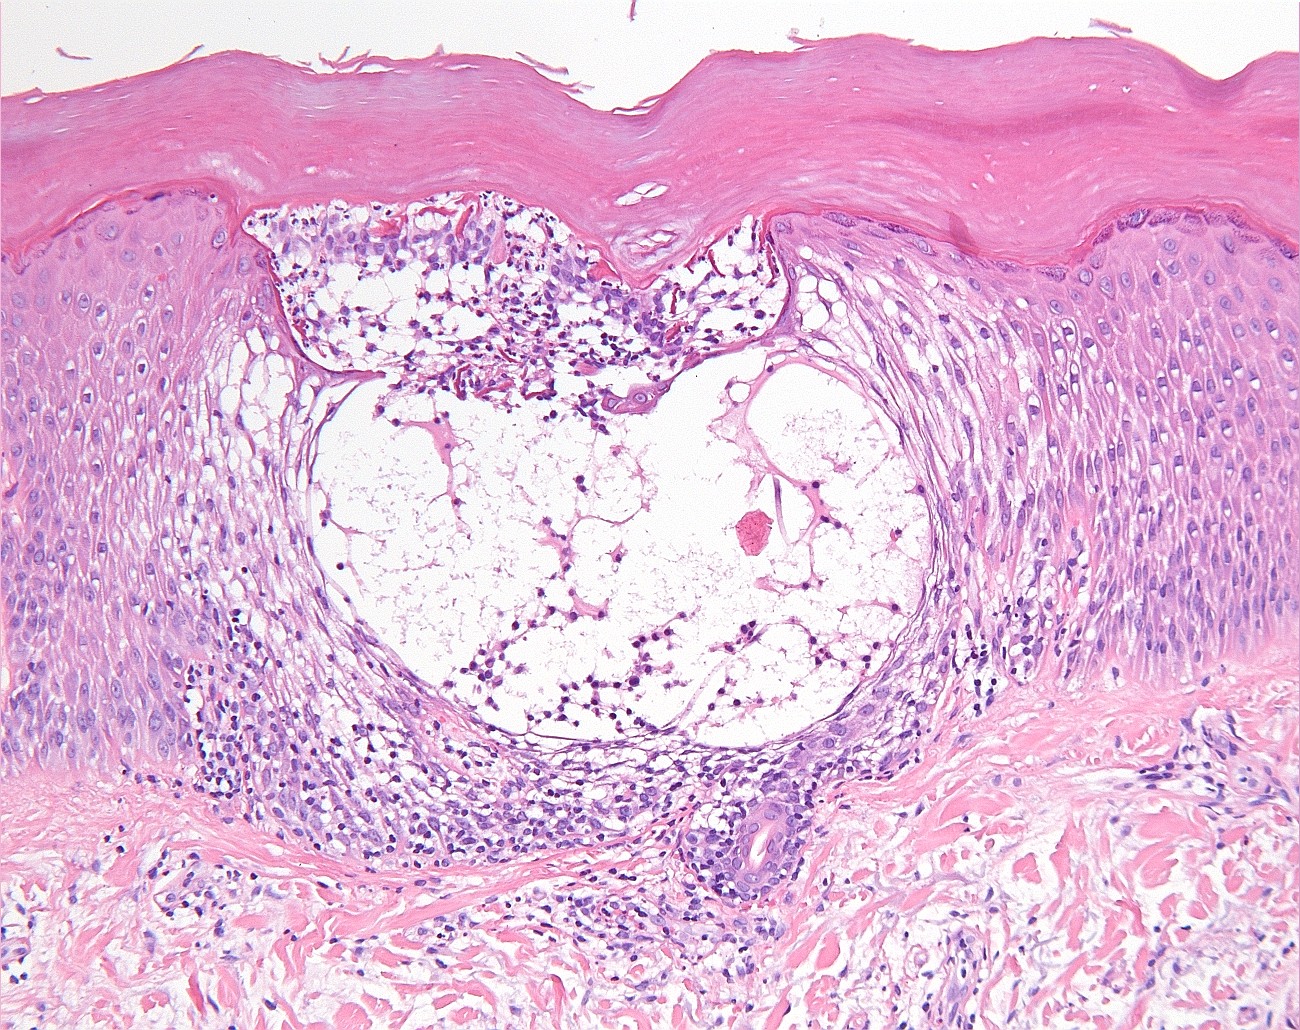

Klinisch beeld:Kleine tot grote spongiotische

vesikels tot bullae, vooral op laterale zijden vingers beide handen, handpalmen

en voetzolen (zelden). Het kan acuut zijn, recidiverend, of chronisch. Gaat

gepaard met jeuk of branderigheid. Bij warm weer is het erger. Soms treedt secundaire

infectie op met als mogelijk complicatie erysipelas of lymfangitis. Bij chronische

varianten kan ook nageldystrofie optreden.

PA:

het histologisch beeld in de fase dat er klinisch vesikels zijn is dat van een

acuut eczeem met spongiose.